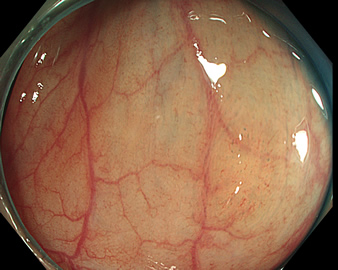

特に、下のような「Ub型(全く凸凹の無い完全に平坦な病変)」は、以前は「ほとんど見つからなかった」のが、TXIを使うようになってから「日常的に」見つかるようになりました。

通常観察 TXIモード

青い色素は追加していません![]()